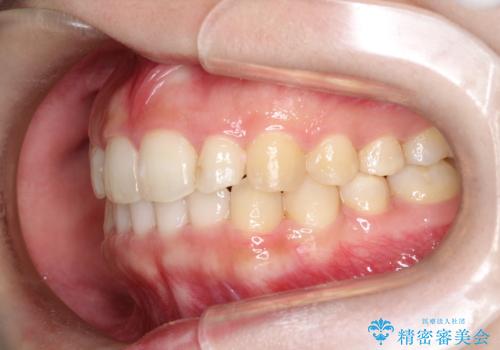

インビザラインでの前歯のガタガタの矯正

- 上下の前歯のがたつきを主訴に来院されました。

歯と歯の間をわずかに削りスペースを作り、インビザラインにて矯正治療を行うこととしました。

使用時間を守っていただけたので、スムーズに矯正を終了することができました。